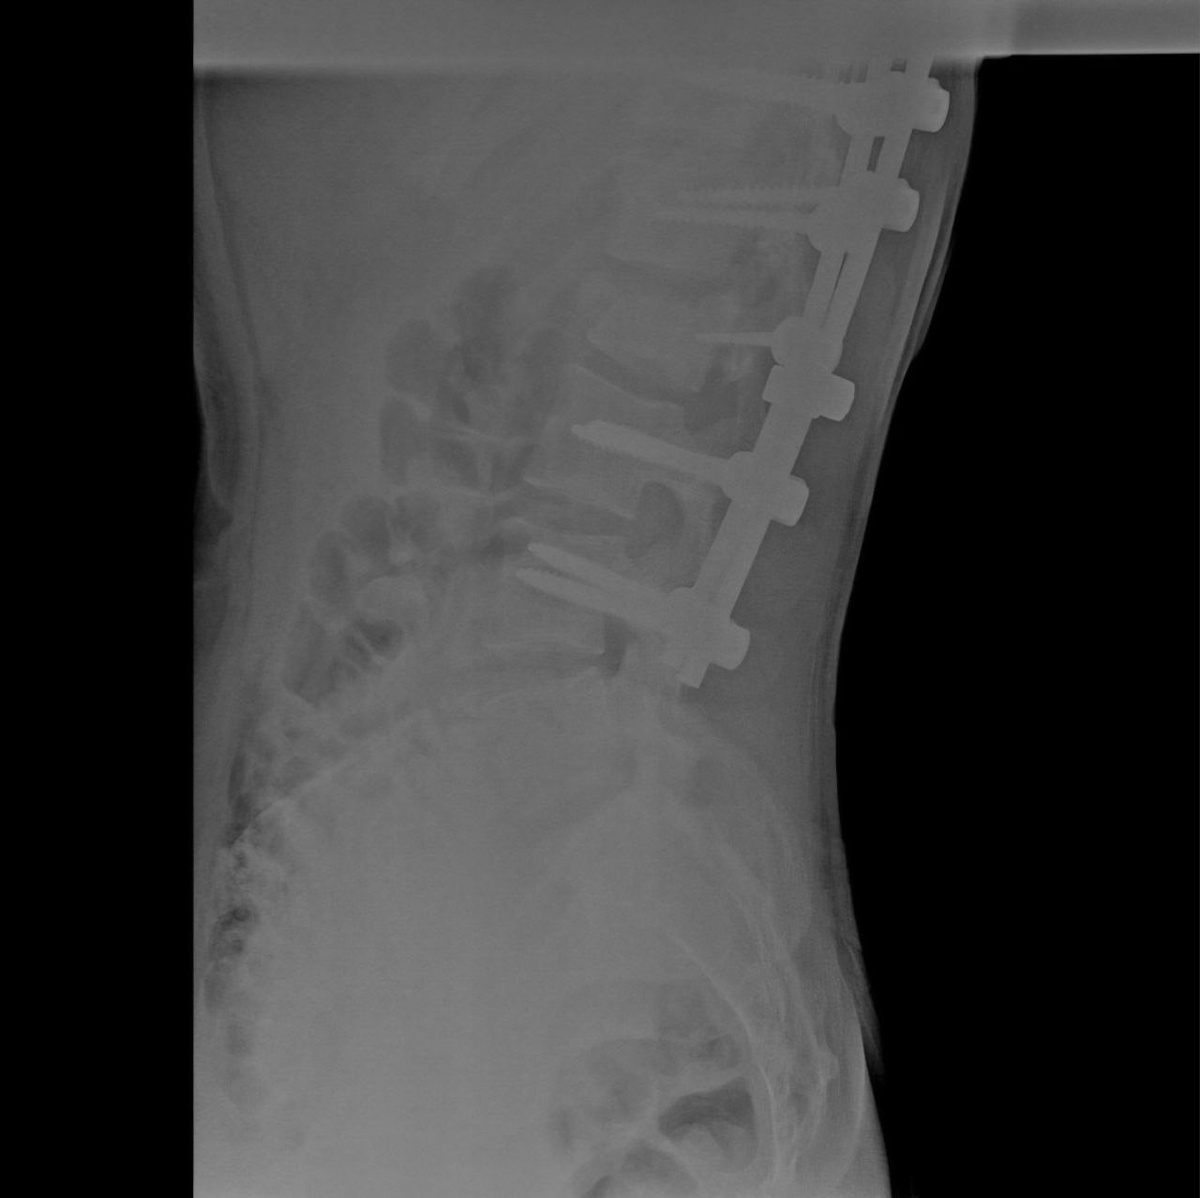

Тогда его срочно увезли в ближайшую райбольницу, а затем в воронежскую больницу скорой медицинской помощи №1. Медики выявили закрытый нестабильный компрессионно-оскольчатый перелом одного позвонка; переломы тела и поперечных отростков двух других позвонков; множественные переломы рёбер с двух сторон; двусторонний малый пневмоторакс (скопление воздуха или газов в плевральной полости, которое приводит к сдавливанию лёгкого, из-за чего оно не может полностью расправиться при вдохе); ушиб обоих лёгких.

В БСМП №1 подростку провели сложнейшую операцию, выполнив стабилизацию пяти позвонков с помощью специальной металлической конструкции из титановых винтов и стержней, удалили задние и передние структуры позвонка из заднебокового доступа.